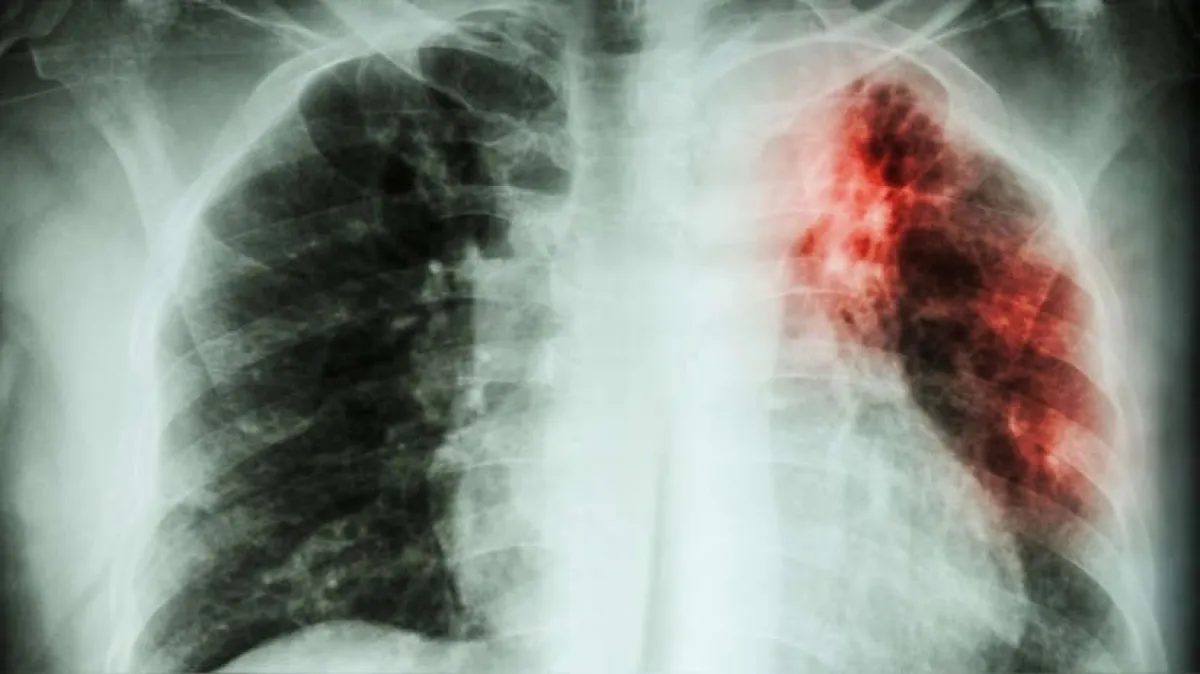

La provincia registró 188 casos en 2024 y 181 en 2025, una diferencia mínima que mantiene el riesgo de contagio. Mientras tanto, el boletín nacional muestra que la enfermedad sigue concentrada en las mismas jurisdicciones de mayor carga, con fuertes contrastes territoriales en todo el país. lunes 24 de noviembre de 2025 | 9:00hs. Misiones cerró el último período con una cifra elevada de casos de tuberculosis, sin un descenso que marque una mejora sostenida. Según el boletín epidemiológico, la provincia registró 188 casos en 2024 y 181 en 2025, un retroceso mínimo. La diferencia interanual, aunque no abrupta, muestra que la carga de la enfermedad se mantiene prácticamente igual. La persistencia de estos niveles implica que el riesgo de contagio sigue siendo significativo, ya que la tuberculosis se transmite por vía aérea y el documento advierte la presencia de “importantes diferencias entre jurisdicciones” en la distribución del total de casos del país . Esto evidencia que, en territorios donde la curva no desciende, la posibilidad de exposición comunitaria permanece estable y sin señales de mejora. En este contexto, los datos oficiales remarcan la necesidad de reforzar las estrategias de vigilancia, búsqueda activa y diagnóstico oportuno para evitar que la actual meseta se transforme en un aumento más marcado durante los próximos ciclos epidemiológicos. Panorama nacional: fuerte concentración y desigualdades territoriales El boletín destaca que, a nivel país, la distribución es profundamente desigual y que “excepto por la provincia de Neuquén, las jurisdicciones con mayor carga son las mismas en ambos períodos” . Entre esas jurisdicciones de mayor peso epidemiológico se encuentran Buenos Aires, CABA, Santa Fe, Córdoba y Salta, que concentran un volumen significativo de casos año tras año. En el extremo opuesto, provincias como La Rioja, San Luis y Tierra del Fuego vuelven a ubicarse entre las de menor incidencia, reforzando los contrastes que el informe describe como “importantes diferencias entre jurisdicciones” . Esta concentración estable en un puñado de distritos -y la permanencia de los de menor carga en el mismo grupo- evidencia que el mapa epidemiológico de la tuberculosis en el país se sostiene prácticamente sin modificaciones estructurales, marcando desigualdades persistentes en el tiempo. Las diferencias territoriales -y el hecho de que los cambios entre años no alteren esta estructura- subrayan la necesidad de políticas focalizadas y una vigilancia más intensiva en los distritos de mayor riesgo. Qué es la tuberculosis y cómo se transmite La tuberculosis es una enfermedad infectocontagiosa causada por la bacteria Mycobacterium tuberculosis. Afecta principalmente los pulmones, aunque puede comprometer otros órganos. Se transmite por el aire, a través de microgotas que se expulsan al toser, hablar o estornudar. El contagio ocurre generalmente en ambientes cerrados, mal ventilados o con contacto prolongado con una persona enferma. Los síntomas más habituales incluyen tos persistente por más de dos semanas, fiebre, sudoración nocturna, pérdida de peso, fatiga y, en algunos casos, tos con sangre. La enfermedad es potencialmente grave, pero tiene tratamiento y cura si se detecta a tiempo. Cómo se trata y qué recaudos se deben tomar ante un contagio El tratamiento de la tuberculosis es gratuito en el sistema de salud público y consiste en una combinación de antibióticos durante un período que suele extenderse entre seis y nueve meses. La adherencia es fundamental: abandonar el tratamiento o tomarlo de manera irregular favorece la aparición de formas resistentes, mucho más difíciles de curar. Una vez iniciado el tratamiento, la persona deja de transmitir la enfermedad después de aproximadamente dos a tres semanas, siempre y cuando mantenga una adherencia correcta.